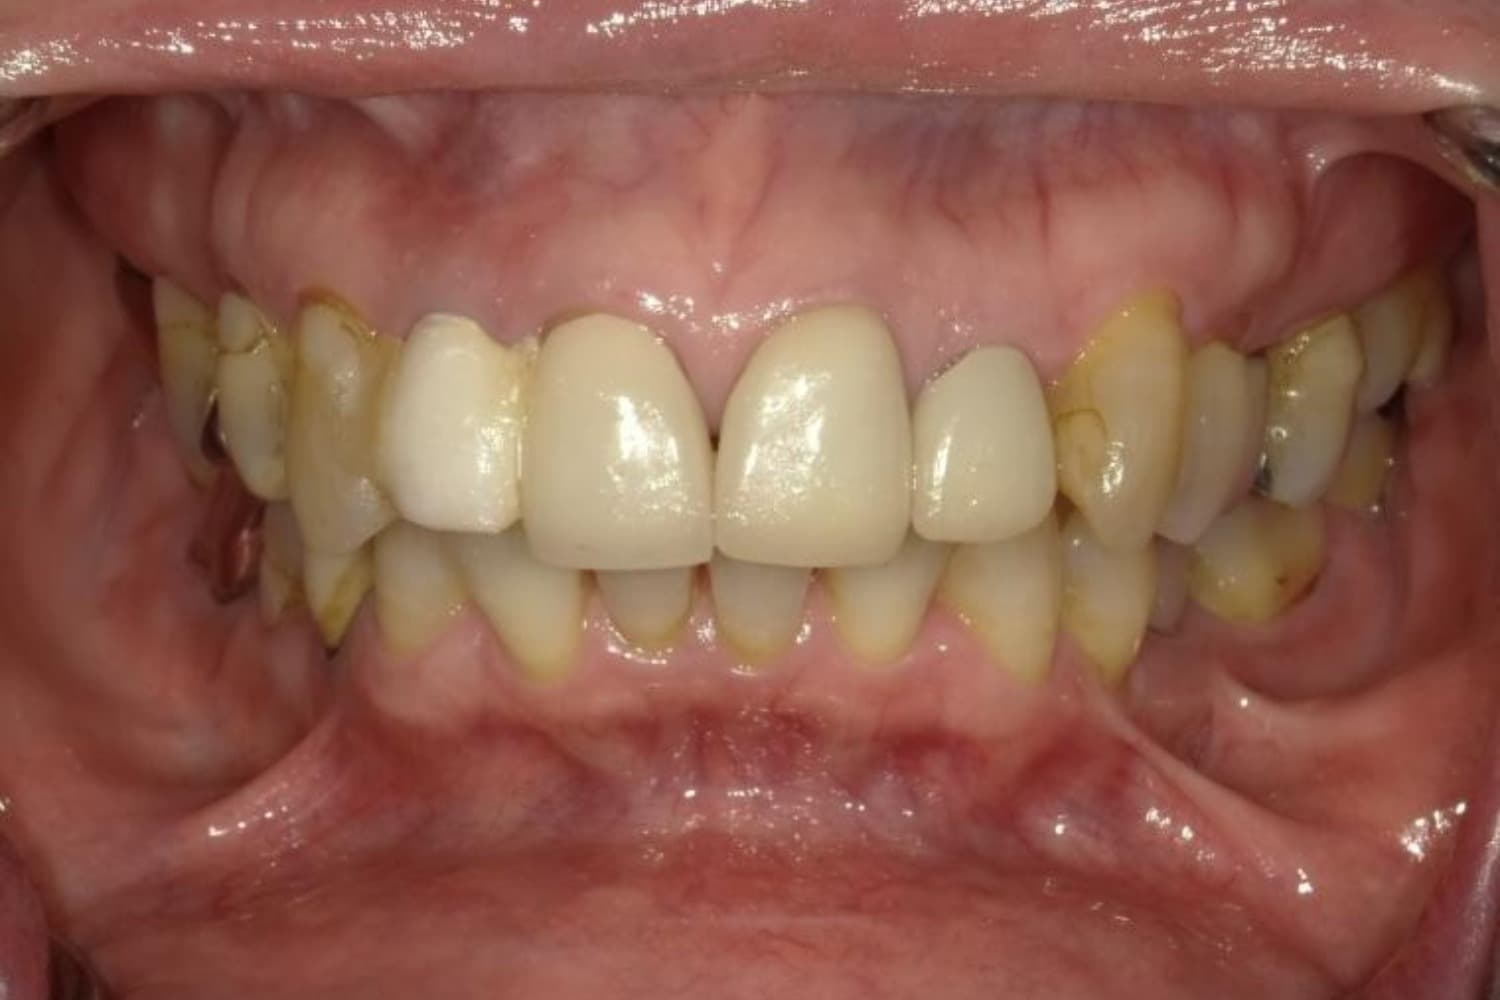

上顎前歯2本欠損症例(2)

Before

After

保存が困難な状態であったため抜歯をおこない、その後インプラントを2本埋入しました。

年齢

67歳

性別

女性

主訴

右上前歯は以前に別の医院で治療中でしたが中断されたため、当院へご相談くださいました。

治療期間

10ヵ月

費用

120万円

副作用・リスク

インプラント治療は外科的な処置を伴い、多少の腫れや痛みが出ることがあります。 多くの場合は鎮痛薬で和らげることができます。